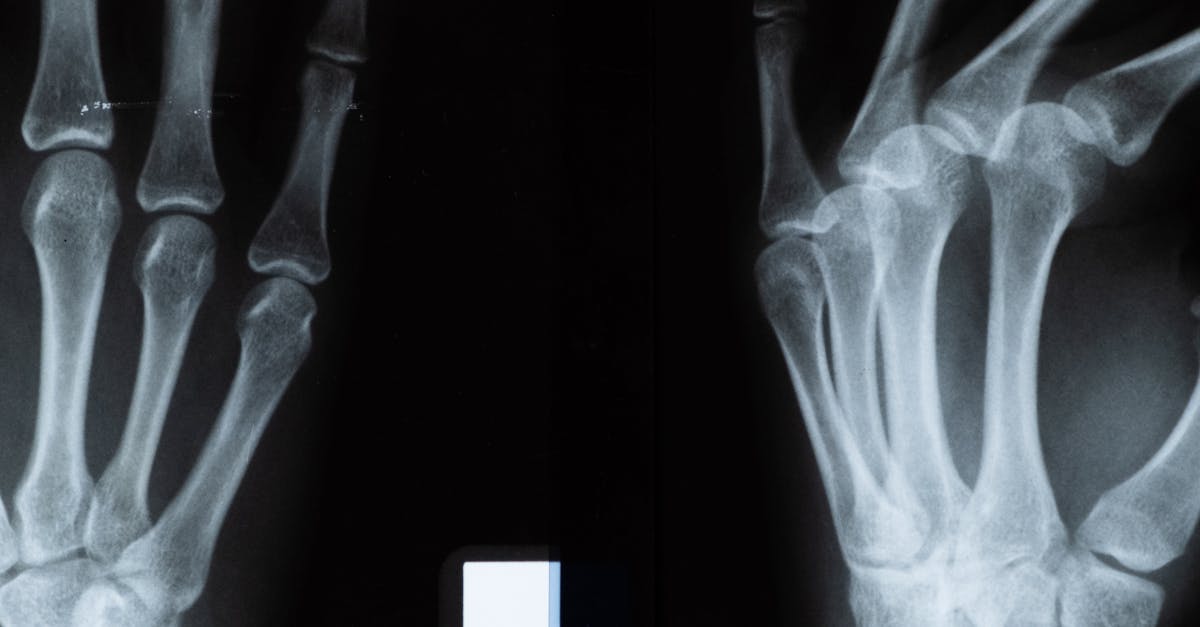

After age 40, the human body undergoes a fundamental shift in bone metabolism that marks the beginning of a gradual but persistent decline in bone density. This biological milestone represents more than just another birthday—it signals the onset of a period where bone resorption begins to outpace bone formation, leading to an annual bone loss of approximately 0.5-1% per year in healthy adults. For women, this process accelerates dramatically during menopause, with bone loss rates potentially reaching 3-5% annually in the first five to ten years post-menopause. Understanding and monitoring the key factors that influence bone density becomes crucial during this phase of life, as the decisions made and lifestyle modifications implemented can significantly impact long-term skeletal health and quality of life. The complex interplay of hormonal changes, nutritional status, physical activity levels, and various health conditions creates a unique landscape of risk factors that require careful attention and proactive management to prevent osteoporosis and reduce fracture risk in later years.

Effective monitoring of bone health after 40 requires a comprehensive approach that combines clinical assessments, laboratory testing, imaging studies, and lifestyle evaluations to identify risk factors early and implement appropriate preventive measures. Bone density testing using dual-energy X-ray absorptiometry (DEXA) scanning represents the gold standard for assessing bone health, with initial screening recommended for all women at age 65 and men at age 70, though earlier screening may be warranted for individuals with risk factors. The frequency of follow-up DEXA scans depends on initial results and risk factors, typically ranging from 1-2 years for high-risk individuals to 3-5 years for those with normal bone density. However, DEXA scanning only measures bone quantity, not quality, leading to increased interest in additional assessment tools such as trabecular bone score (TBS), which evaluates bone microarchitecture, and biochemical markers of bone turnover that can provide insights into the rate of bone remodeling. Laboratory monitoring should include assessment of vitamin D status (25-hydroxyvitamin D), calcium levels, parathyroid hormone, and markers of bone turnover such as C-terminal telopeptide (CTX) and procollagen type 1 N-terminal propeptide (P1NP). Regular evaluation of modifiable risk factors includes assessment of dietary intake, physical activity levels, medication use, and lifestyle factors, with particular attention to changes that may impact bone health. Preventive measures should be individualized based on risk assessment and may include dietary modifications to ensure adequate calcium and vitamin